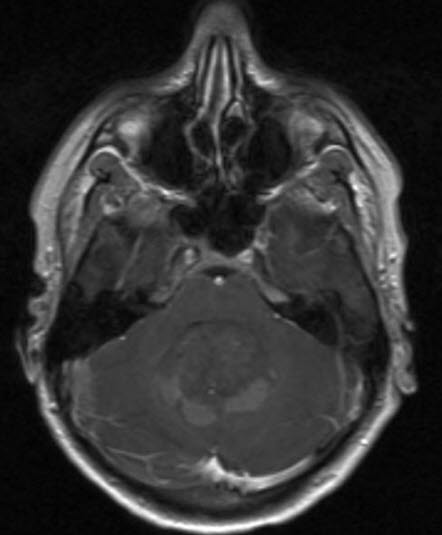

Medulloblastom, aksialt snitt

Gjengitt med tillatelse av Radiologisk avdeling, Universitetssykehuset Nord-Norge